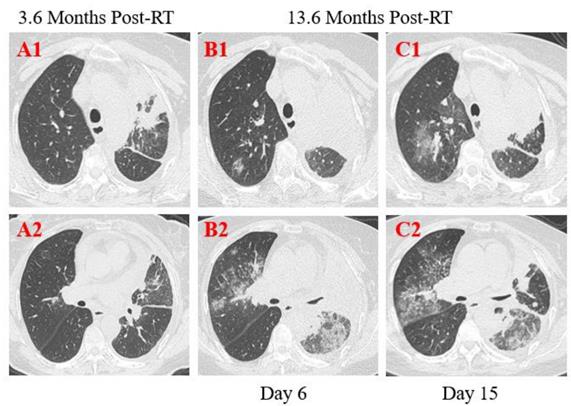

Patient 4: A 39-year-old male was diagnosed with nasopharyngeal carcinoma (T2N2M0) treated with radical concurrent chemoradiotherapy in June 2013. He was admitted to the hospital with a positive result of the swab nucleic acid test for COVID-19 on February 14, 2020. The patient had transient diarrhea 10 days ago but no other symptoms afterward. The patient traveled to Zhuhai from the infected area (Wuhan, China) and had close contact with the confirmed COVID-19 patient, his aunt. At admission, both lungs were clear on auscultation. Laboratory studies showed normal blood routine results. Reslus of influenza A and B antigen screening for this patient were negative. The T lymphocyte subsets test showed a slight drop in CD4+ and CD8+ T cell counts. Chest CT images were obtained on the 10th day after symptom onset and showed that there were multiple ground-glass opacities of the lower lobes of both lungs peripherally and subpleurally (Figure 5. A2). A few linear opacities were presented in upper lobe lower lingual segment of the left lung (Figure 5. A3) within the ionizing radiation area, indicating radiation fibrosis. After 8 days of anti-viral therapy with resochin and supportive treatment, follow-up CT scans demonstrated a significant improvement in the extent and density of the ground-glass opacities (Figure 5. B2), but found a new focal ground-glass opacity (GGO) in the upper lobe of right lung (Figure 5. A1, B1). Treatment continued until the result of the swab test became negative.

Transverse unenhanced thin-section serial CT scans from a 39-year-old male with COVID-19 pneumonia. Chest CT images on the 10th day after symptom onset demonstrated multiple ground-glass opacities of the lower lobes of both lungs peripherally (A2), and a few linear opacities in upper lobe lower lingual segment of the left lung (A3). Follow-up CT at the 18th day demonstrated significant improvement in the extent and density of the ground-glass opacities (B2), and appearance of new focal ground-glass opacities of the upper lobe of right lung (B1).